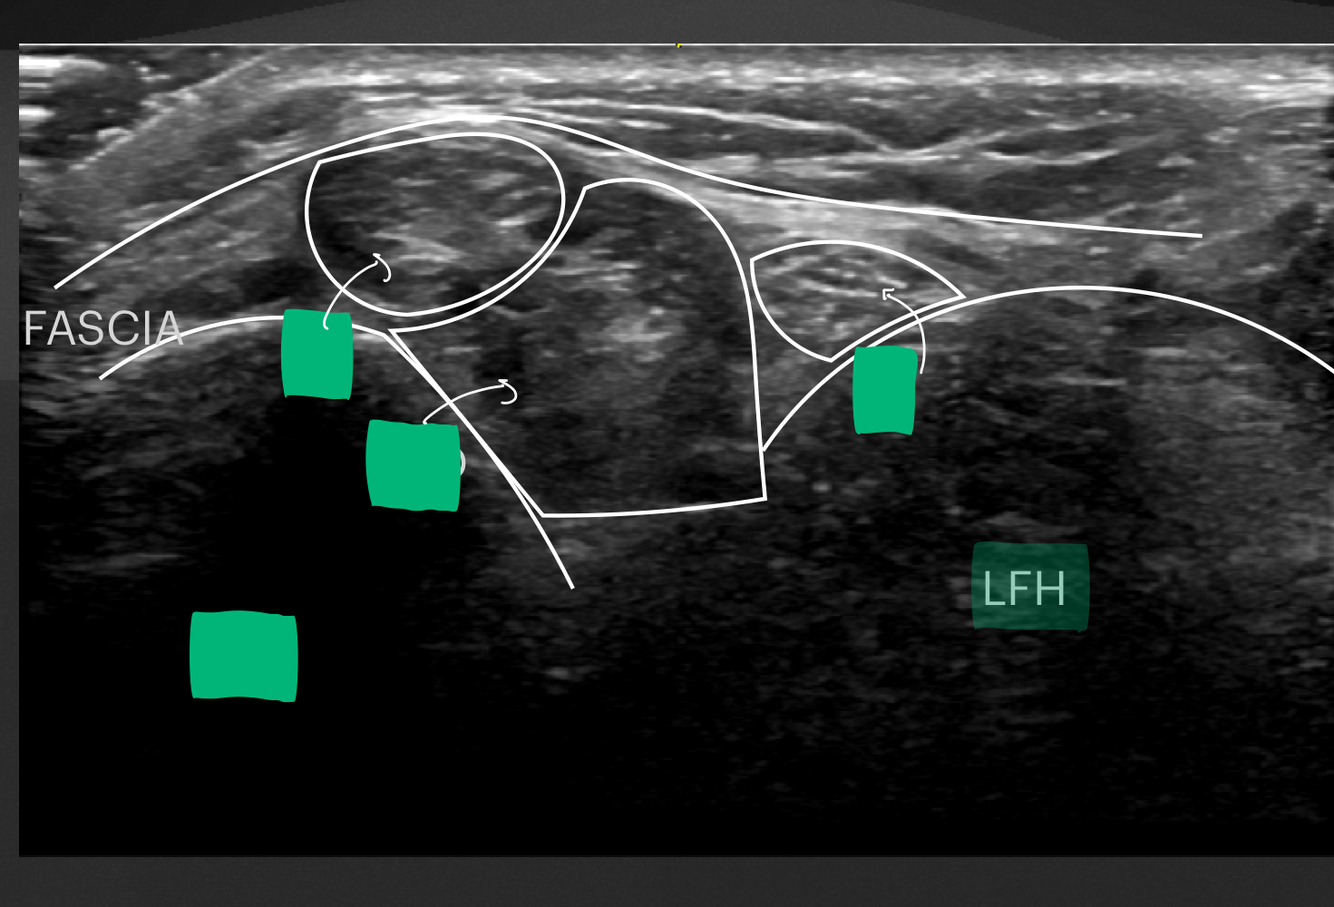

2

Q

Identifier les 6 structures situées en médial de la cheville